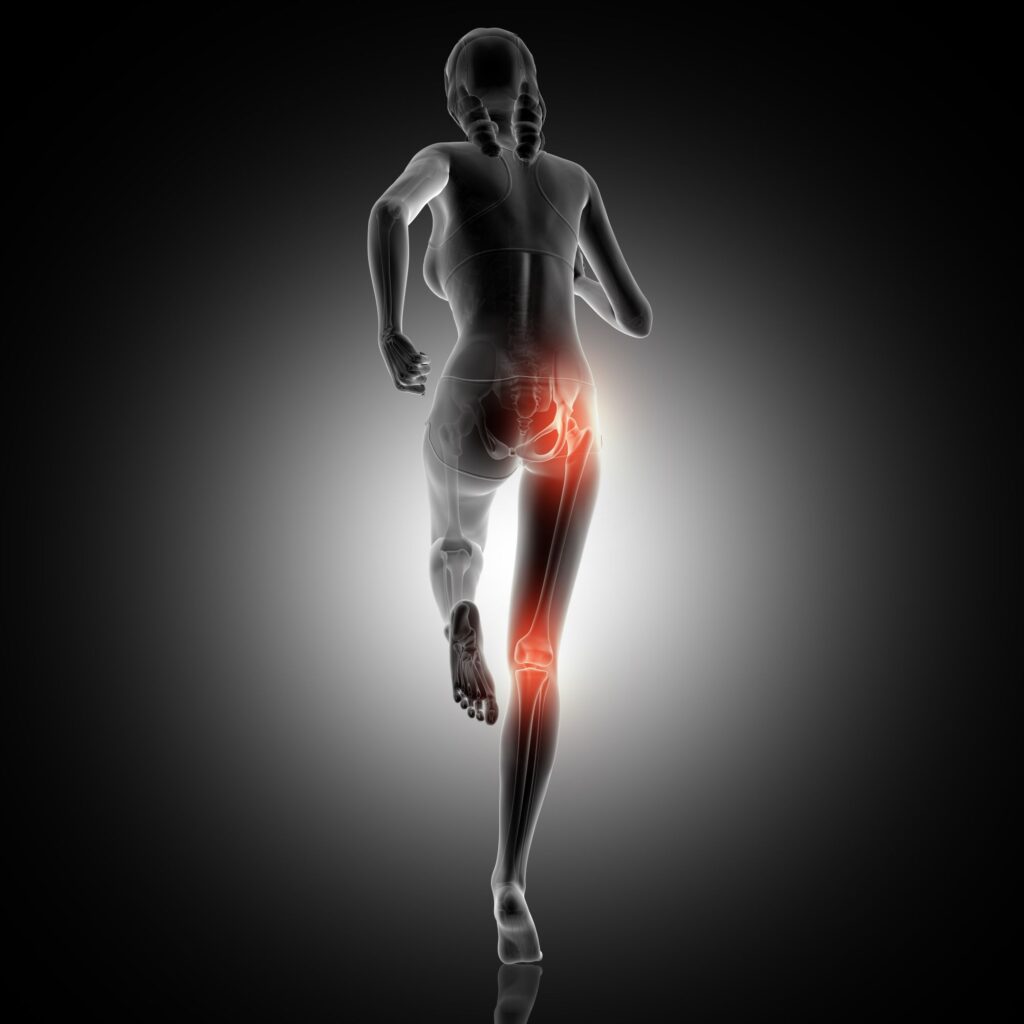

O músculo piriforme é um pequeno músculo localizado na região glútea que desempenha um papel fundamental na estabilização da articulação do quadril e movimentação da perna. Quando o piriforme está fraco ou tensionado, pode levar a problemas como a síndrome do piriforme, uma causa comum de dor ciática. Portanto, fortalecer e manter o piriforme flexível é crucial para a saúde do quadril e alívio da dor. Abaixo, você encontrará dicas valiosas para fortalecer este importante músculo.

Antes de mergulhar nos exercícios, é útil entender a localização e função do piriforme. Ele se estende desde o sacro (a base da coluna) até o trocânter maior do fêmur (osso da coxa). Quando o piriforme se contrai, ele ajuda a rodar a coxa externamente.